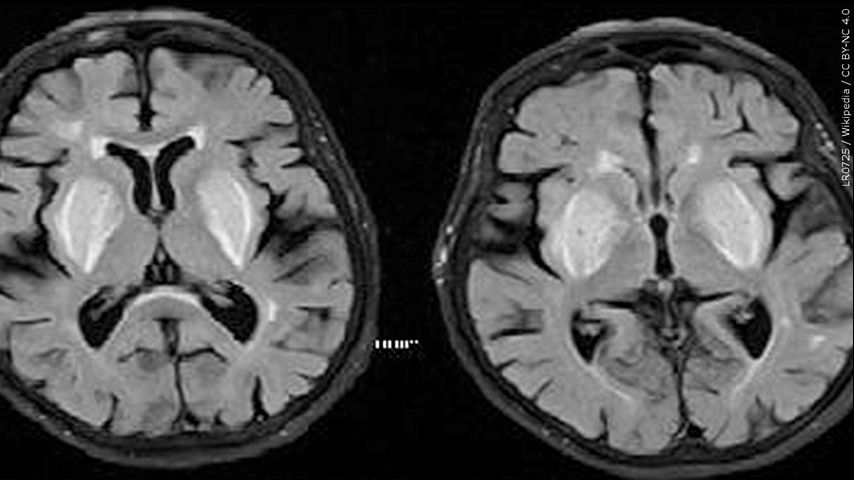

BATON ROUGE — People at risk for dementia may want to check out the Mediterranean diet, as a new study finds that it lowers the risk of dementia.

It is especially effective for people with the APOE4 gene, considered a major risk factor for Alzheimer's disease.

It lowered the probability of developing dementia by at least 35%.